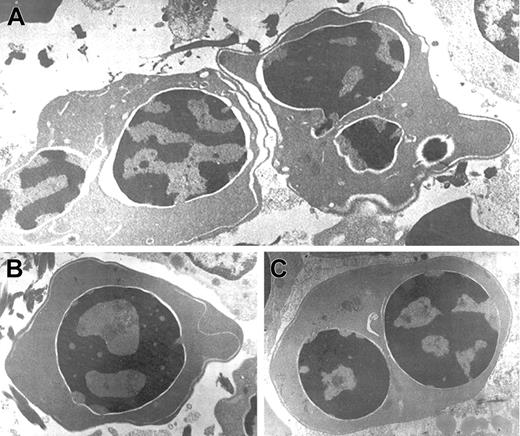

Electron microscopic aberrations were more prominent in late erythroblasts (Figure 2). The nuclear outline was often undulated or lobulated, and the nuclear membrane–associated heterochromatin was frequently absent over large areas of the nuclear membrane. In some cells, the heterochromatin was spongy and showed numerous “punched out” areas. The main cytoplasmic anomaly was the presence of abundant cytoplasmic membranes that are composed of excessive smooth endoplasmic reticulum. These characteristic cisternae usually ran parallel beneath the cell outer membrane producing the so-called “double membrane.” The dilatation of the space between the 2 layers of these cytoplasmic membranes was frequently observed, as was the dilatation of the space of the nuclear membrane.

Electron micrographs of several bone marrow late erythroblasts.

Multinucleate erythroblasts showing striking “double membranes” with partial dilatation of the intramembranous space (A). Erythroblasts revealing nondilated cisternae (B,C). Late erythroblast depicting spongy heterochromatin with numerous “punched out” areas (B). Binucleate erythroblasts showing large areas of nuclear membrane without attached heterochromatin (C). Uranyl acetate and lead citrate stain. Original magnification: A, × 10 600; B and C, × 18 000).

Electron micrographs of several bone marrow late erythroblasts.

Multinucleate erythroblasts showing striking “double membranes” with partial dilatation of the intramembranous space (A). Erythroblasts revealing nondilated cisternae (B,C). Late erythroblast depicting spongy heterochromatin with numerous “punched out” areas (B). Binucleate erythroblasts showing large areas of nuclear membrane without attached heterochromatin (C). Uranyl acetate and lead citrate stain. Original magnification: A, × 10 600; B and C, × 18 000).